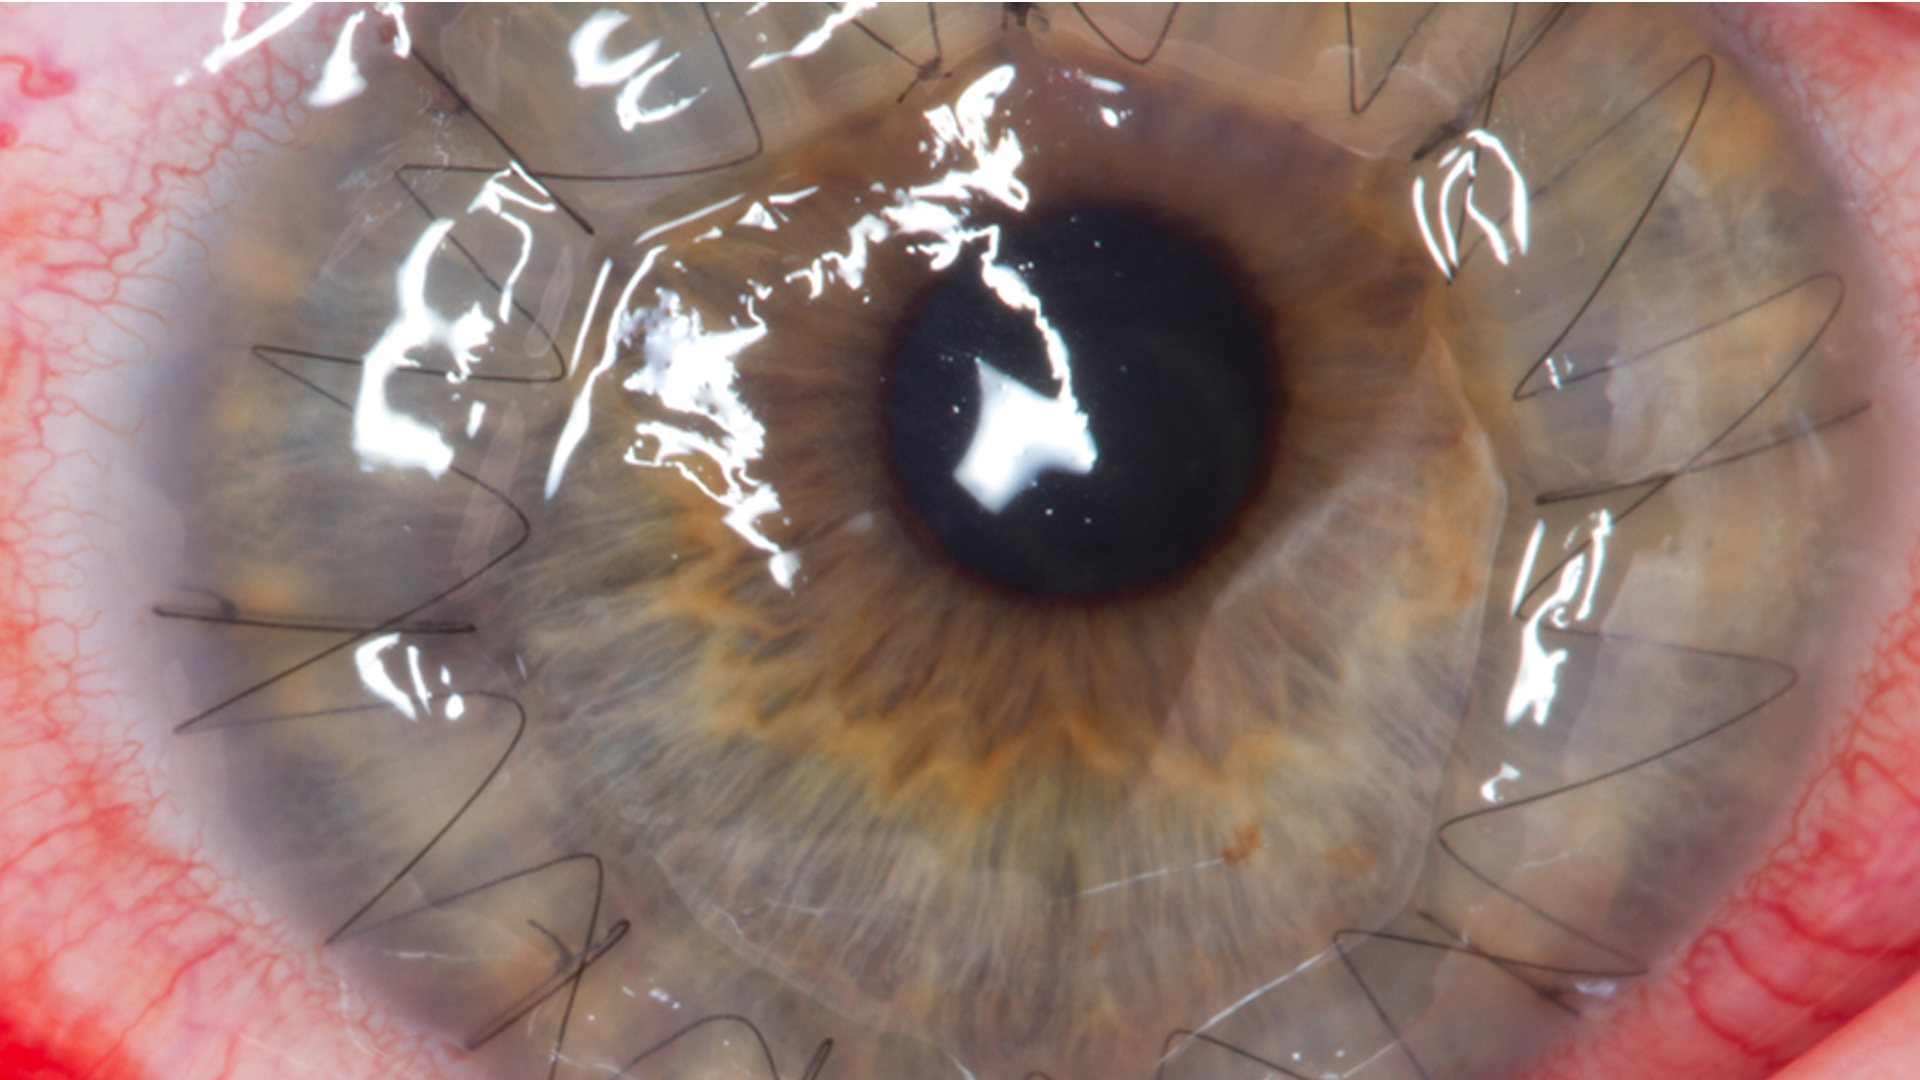

(PDF) Intrastromal fluid drainage with air tamponade Anterior segment Corneal Fluid Drainage Aside from discharging crucial functions, there is another peculiarity these layers share—it is not known how they transport fluid. a glaucoma drainage implant is a small device placed in the eye to treat glaucoma. the technique entailed anterior segment optical coherence tomography guided intrastromal fluid drainage through. it regulates eye pressure by draining aqueous humor, a fluid. Corneal Fluid Drainage.

Figure 1 from A microinvasive technique for management of corneal edema Corneal Fluid Drainage There are several types of glaucoma drainage implants. it regulates eye pressure by draining aqueous humor, a fluid produced inside the eye that nourishes the cornea and lens. fluid transport in general and in the corneal endothelium. a glaucoma drainage implant is a small device placed in the eye to treat glaucoma. The endothelium is but one. Corneal Fluid Drainage.